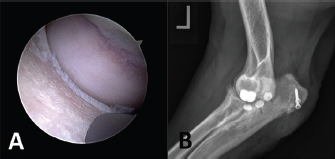

In all five cases with persistent lameness and pain, a second look arthroscopy was carried out. In two cases, an extension of a full-thickness chondral defect caudal to the ulnar implant was apparent and treated by implantation of one (n=1) or two (n=2) additional UImpl just caudal to the initial implant along the ulnar trochlea, using the modified caudo-medial approach and standard CUE implantation technique (Fig. 7). Further healing was uneventful, and at the last follow-up examination 2 and 10 months after revision surgery, both cases achieved an acceptable outcome with a LOAD score of 18.

Fig. 7. Case with persistent lameness and pain 6 months after CUE procedure. (A) Second-look arthroscopy showing an extension of full-thickness chondral defect caudal to the ulnar implant and (B) Medio-lateral radiographic view after revision surgery and implantation of two additional medium-sized ulnar implants.

In two cases, full-thickness cartilage loss was presented caudal to the ulnar implant on the second-look arthroscopy, indicating erosive wear of the HImpl at the ulnar trochlea. It is interesting to note that both elbows had relatively low preoperative IEWG scores as well as a good ROM. After implantation of one or two additional ulnar implants, respectively, the lameness improved significantly and no signs of pain on palpation were apparent in either case at the follow-up examination. The obvious improvement in clinical function following implantation of the additional implant(s) leads us to the conclusion, that under some circumstances, resurfacing with only one implant might not be enough. Whether this is related to an increased ROM in dogs with mild degenerative joint disease, allowing the HImpl to contact caudal to the ulnar implant position, or if this is the result of some form of technique related impingement of the HImpl on the ulna is uncertain. However, both on arthroscopy and on radiographic examination, implant position appeared to be correct. In another two cases, progressive bone eburnation with a groove-shaped bone defect along the MCP, as well as signs of polyethylene implant wear and/or plastic deformation, was evident on second-look arthroscopy. Radiographic examination was uneventful in both cases, making more advanced imaging, preferably arthroscopy necessary to pick up this type of complication. We suspect the axial border of the HImpl to have caused those grinding lesions. Because the majority of the humeral implants were not implanted parallel to the ulnar implant, we expected significant obliquity of the HImpl to be the underlying cause. However, when compared to the median deviation of 10.8°, both implants appeared to be properly oriented. Overall, the degree of HImpl mal-angulation did not correlate with the functional outcome or the occurrence of complications in our case series. This should not be taken as a proof that HImpl position and/or orientation are not of clinical significance, because the small sample size as well as the way we assessed implant orientation, which might not mimic the true contact situation during weight-bearing (Burton et al., 2013; Goodrich et al., 2014), are considerable bias. Ex vivo biomechanical testing of implant contact following CUE procedure, as well as prospective evaluation of implant contact and related osteochondral or implant wear in a larger number of clinical cases by means of second-look arthroscopy is warranted. For the first time, we report on septic arthritis and related implant loosening, with the latter being undetectable on the follow-up radiographs. After thorough lavage of the joint, and explantation of the loose implant and subsequent antimicrobial therapy, the infection was resolved successfully despite the retained humeral and second ulnar implant. Over reaming and implantation of a larger implant proved to be an effective revision strategy supporting the statement of Franklin et al. (2014) that CUE is a bone sparing procedure offering more exit strategies than just implant removal with a fusion of the joint or limb amputation in case of septic loosening.